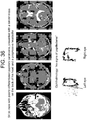

- Case 5 ( Figure 27 ) The patient is a 63 year old male with diabetes, hypertension, hypercholesterolemia, atrial fibrilliation on coumadin, congestive heart failure, post-traumatic stress disorder, renal failure on dialysis, chronic obstructive pulmonary disease and coronary artery disease. He presented with confusion while receiving hemodialysis for his renal failure. Ophthalmic history was significant for proliferative retinopathy. He had visual acuity of 20/25 in the right eye and 20/40 in the left eye. On physical examination at presentation he was neurologically well, without neglect or pronator drift. Extraocular movements were intact, pupils were equal. Head CT demonstrated a right sided mixed-density subdural hemorrhage. Eye tracking was performed. Coumadin was stopped and fresh frozen plasma administered. Two days after presentation twist-drill drainage was performed and 176 cc of subdural fluid was evacuated. The patient remained neurologically well and returned to his assisted living residence two days later.

- Perimesencephalic cistern compression (on immediate preoperative CT scan): Right cistern 36% of baseline, left cistern 29% of baseline.

- Scatterplots of the entire time series were created by plotting the 100,000 (x,y) pairs representing the two orthogonal components of the instantaneous angle of pupil reflection over time to create 'box trajectories' that reflected the temporal nature of the pupillary movement.

- these figures look like boxes, reflecting the timing of the aperture as it moved around the screen ( Figure 20 ).